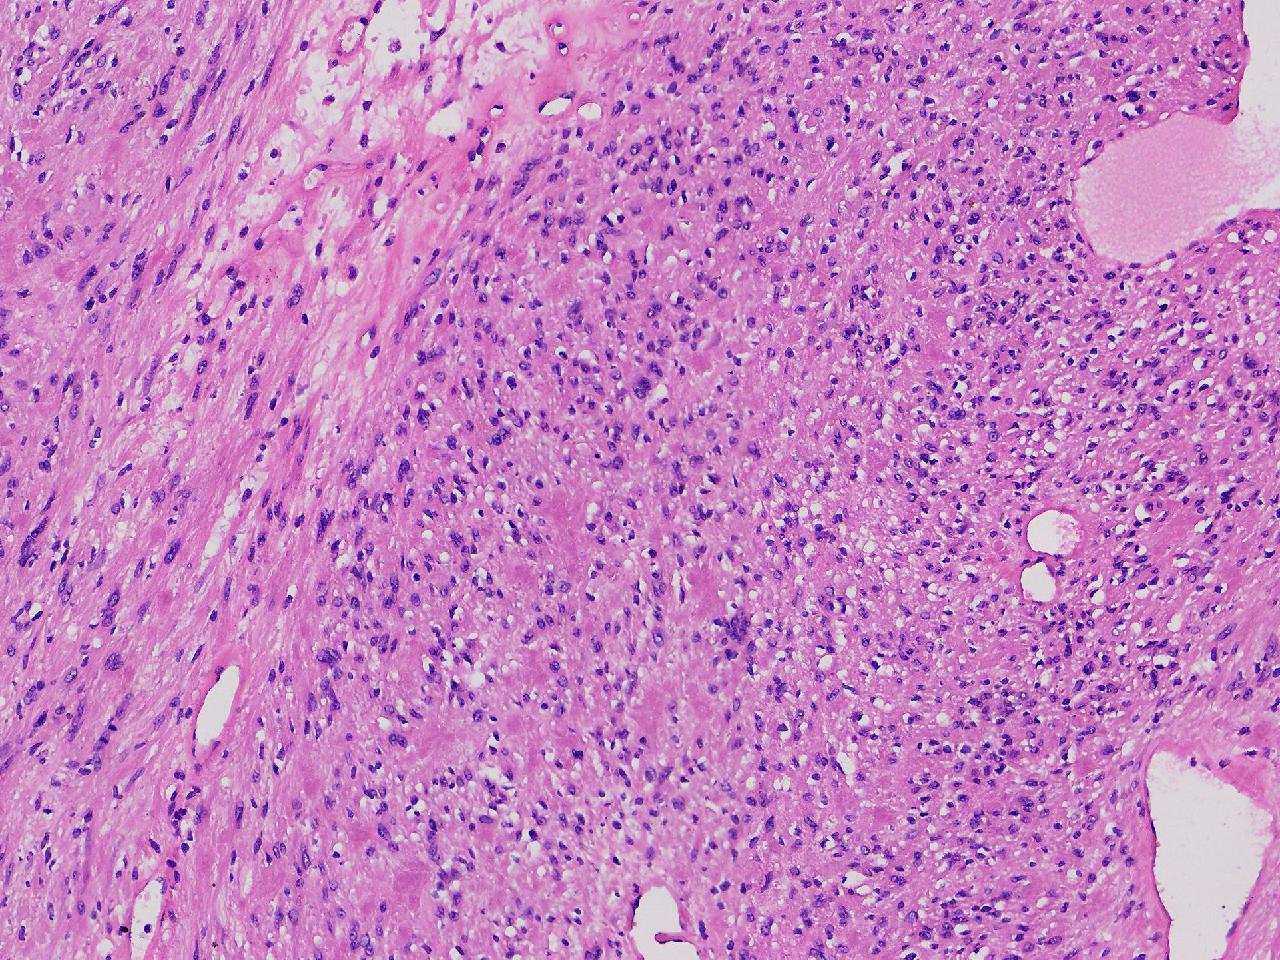

血管平滑肌瘤? 其他?

性别

女

年龄

76岁

临床诊断

右侧腰臀部皮下肿物

一般病史

右侧腰臀部皮下肿物1年余,无明显不适,逐渐增大。

标本名称

大体所见

卵圆形肿物一个,直径1.6厘米,上附皮肤。肿物切面灰黄实性,质中等。

考虑:结节性筋膜炎

完整的包膜。 首先还是考虑神经鞘。

神经鞘瘤。

建议除外平滑肌瘤,做IHC是更好的鉴别方式